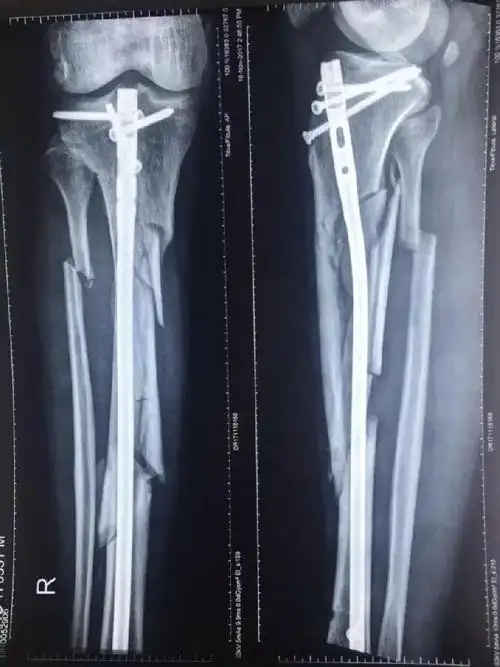

煤矿作业不慎 重物砸断右腿神经 小伙险断肢